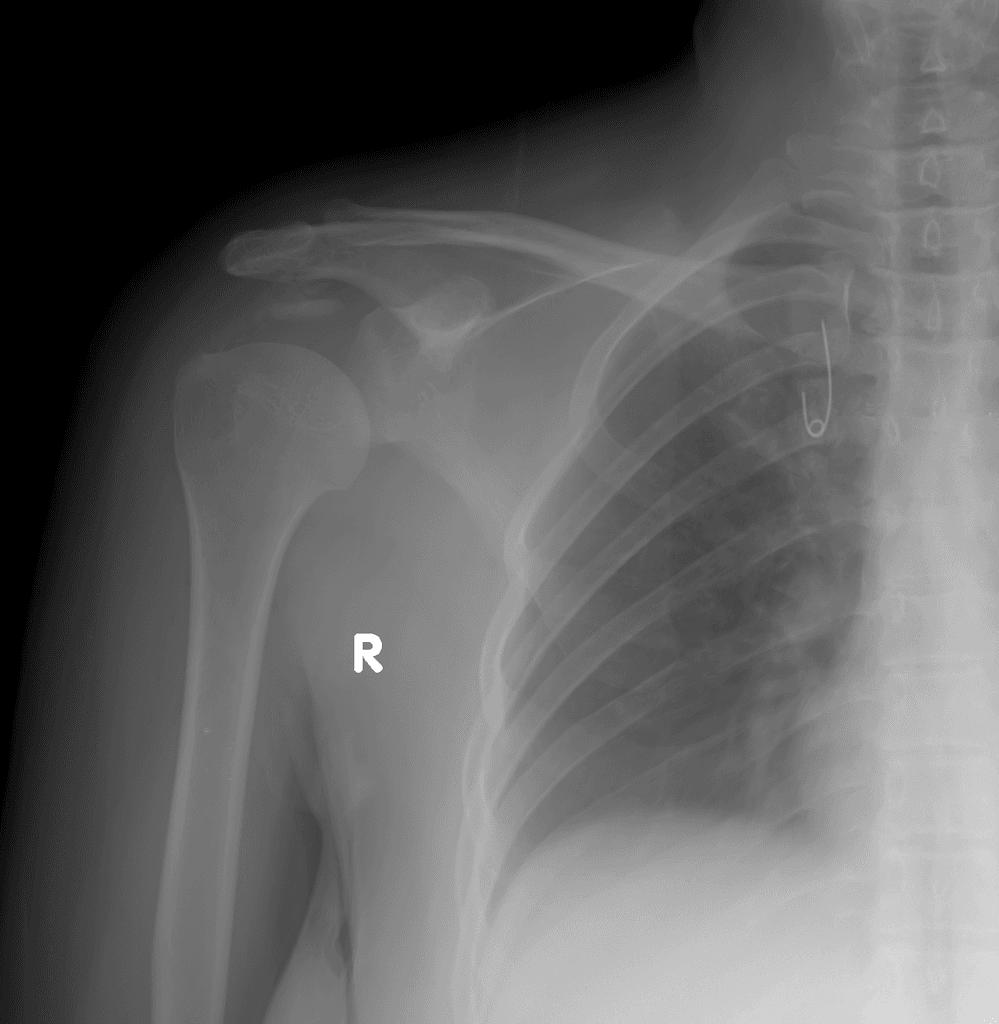

Hình X-quang (X-ray) tư thế trước-sau (AP) khớp vai trái này cho thấy một gãy ngang (transverse fracture) cổ phẫu thuật xương cánh tay (surgical neck of the humerus) kèm theo lún các mảnh gãy (impaction of fragments). Có sự di lệch xuống dưới (inferior displacement) của chỏm xương cánh tay (humeral head) so với ổ chảo (glenoid). Hình ảnh này (bán trật giả - pseudosubluxation) thường được thấy kèm theo gãy xương (fracture) và gợi ý tràn dịch khớp (joint effusion). Có mức mỡ-dịch (fat-fluid level) phù hợp với tràn máu mỡ khớp (lipohemarthrosis). Điều này cho thấy có tổn thương nội khớp (intraarticular injury).

Tràn máu mỡ khớp (lipohemarthrosis) được chú thích.

Tràn máu mỡ khớp (lipohemarthrosis) được thấy trên phim X-quang thường quy (plain radiographs) là không phổ biến ở khớp vai (glenohumeral joint), mặc dù trong một nghiên cứu, nó được thấy trong 25% các trường hợp. Nó được báo cáo lần đầu tiên vào năm 1962 (so với năm 1929 đối với tràn máu mỡ khớp gối - knee lipohemarthrosis). Nó chỉ được thấy trên các tư thế chụp đứng (erect views). Tràn máu mỡ khớp (lipohemarthroses) cũng đã được mô tả ở khớp khuỷu (elbow) và khớp háng (hip).

Lưu ý rằng một mức dịch-dịch (fluid-fluid level) có thể được thấy trong một tràn máu khớp đơn thuần (simple hemarthrosis) trên MRI. Lớp dịch phía trên phải thể hiện các đặc điểm từ tính của mỡ (magnetic characteristics of fat) (ví dụ: giảm tín hiệu trên các chuỗi xóa mỡ - fat-sat sequences) trước khi có thể gọi đó là tràn máu mỡ khớp (lipohemarthrosis).